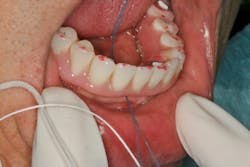

The patient whose bridge is shown in Figure 2 returned to her dentist after the final bridge was placed complaining of speech difficulty and pain. The dentist told her everything was normal and that she needed to adapt to the bridge. Three months later, the patient presented to my office. The speech issue was legitimate in my opinion (that’s a story for another day), but I was concerned about the sensation of pain.

I removed the bridge to find the intaglio packed with food debris. The patient’s tissue was inflamed (figure 3), and she had developed a fungal infection. This could have been avoided with better presurgical preparation, adequate bone reduction, and proper vertical space development, which would have allowed the lab to make a hygienic intaglio (figure 4). Note the smooth and flowing intaglio surface in Figure 4. This is a bridge that can be easily maintained by the patient and hygienist.

Figure 3: Inflamed tissue from an inability to clean under the bridge